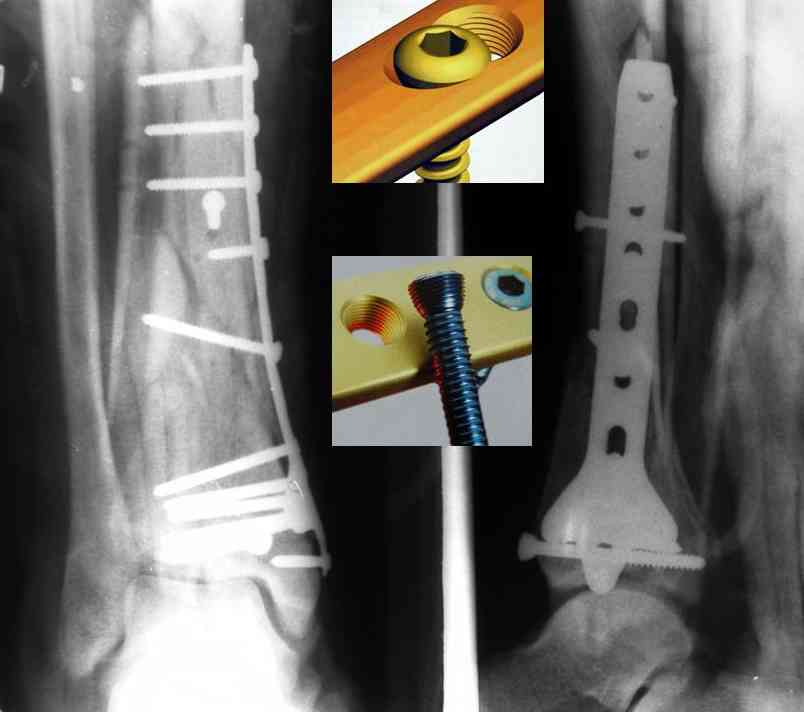

Послала ещё два снимка, если не пройдут, пошлю ещё. Дрягин. Если есть вопросы, готов ответить.